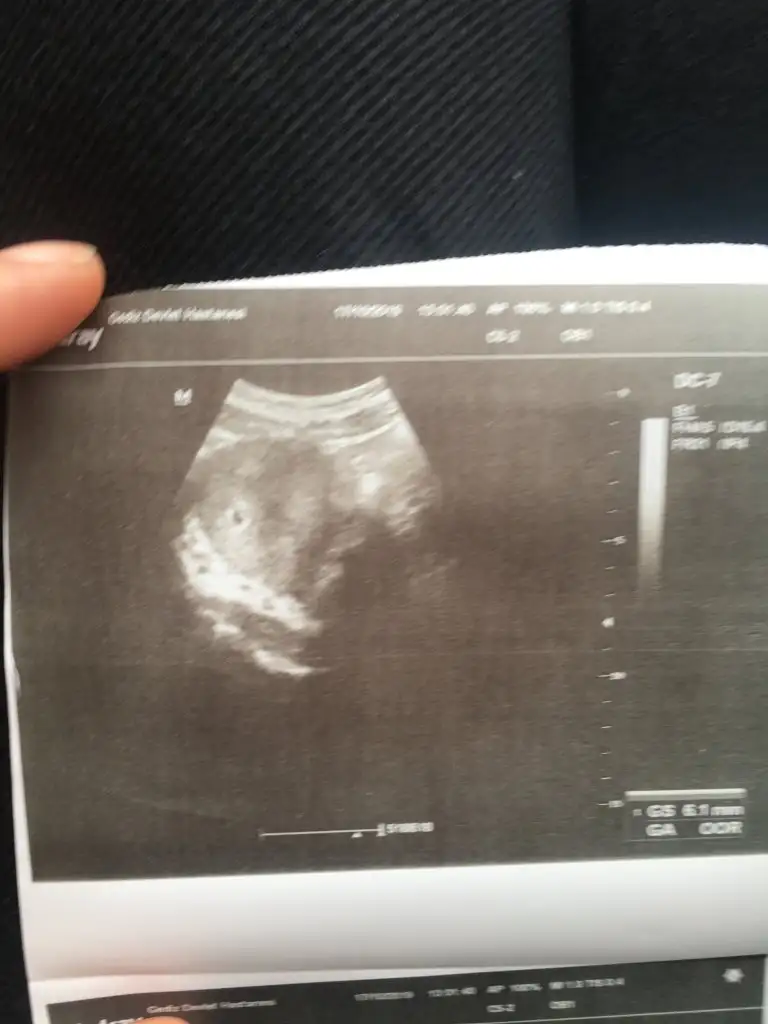

Canımmm cok teşekkür ederim doktordam geldim beta takip edilecek bir süre dedi kese için cok erken dedi. Bu bekleyiş hamileliği beklemekten sanırım daha stresli olacak. Saglık sıhhat versin Rabbim. Sana da nasip etsin inşallah şu mubarek gundeMEVAMMMMMMMMM GÖZÜMÜZ AYDIN OZAMANNNNNNNNNNN

Maşallah canım en son degerin kaçtıKızlar doktora geldim bugün kan veririm diye ama kese göründü 5haftalık miniğim

Ohh ne guzel canimm ☺ tam 5 haftalikken mi goruluyor canimKızlar doktora geldim bugün kan veririm diye ama kese göründü 5haftalık miniğim❤❤❤

Canım valla ilk yaptığımda 42.3dü bugünde kpntrole gittim kan veririm diye düşünüyodum kese göründüğü için kan vermene gerek yok dedi doktorMaşallah canım en son degerin kaçtı

42.3 ne zaman dı canım o zamnCanım valla ilk yaptığımda 42.3dü bugünde kpntrole gittim kan veririm diye düşünüyodum kese göründüğü için kan vermene gerek yok dedi doktor3hafta sonra kalp atışını duyarız dedi Bakalım şimdi iyi bi doktor araştırıyorum doğumumu falan yapıcak nasip olursa inşallah

Evet 5hafta dedi doktor canımYa ben kan vereyim değer yükselmişmi diye gitmiştim 10gün önce 42.3 çıkmıştışimdi yine değere bakarız diye gittim ultrasondan baktı kese görünüyor dedi kan vermene grek yok dedi